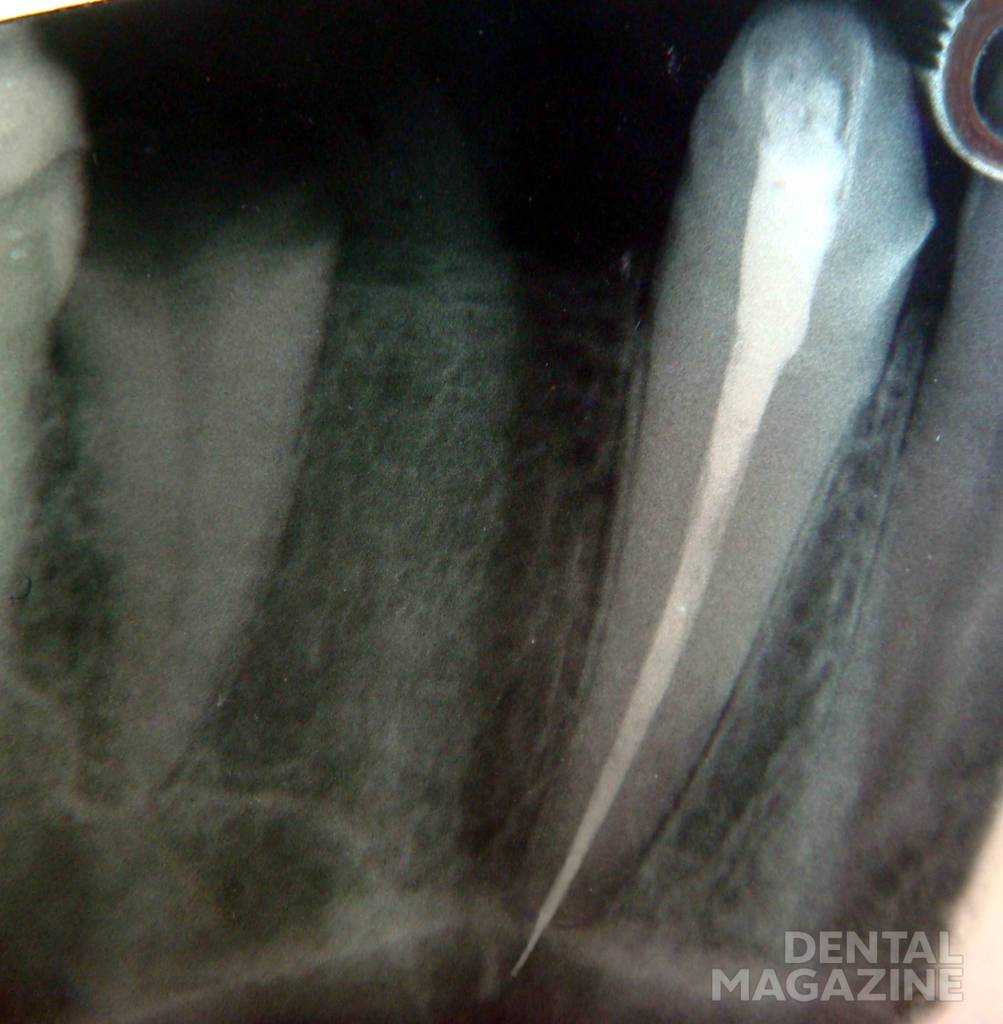

Выталкивание гуттаперчевого штифта за апекс может быть следствием неправильного определения рабочей длины и/или неверного выбора размера основного штифта (рис. 11).

Рис. 11. Выведение гуттаперчевого штифта за верхушку корня.

Выведение гуттаперчи за пределы верхушки корня возможно в процессе латеральной конденсации гуттаперчи (рис. 12).

Рис. 12. Латеральная конденсация штифтов.

Меры профилактики: контроль рабочей длины на всех этапах эндодонтического лечения; грамотное формирование корневого канала; сохранение целостности анатомического (физиологического) сужения.

Если выведение небольшого количества силера за пределы апикального отверстия может не вызывать проблем, поскольку он достаточно быстро резорбируется, то выведенная за верхушку гуттаперча, которая сама по себе биологически инертна, способна длительно поддерживать воспаление в тканях апикального периодонта, являясь механическим раздражителем.

Продольный перелом корня возможен в процессе латеральной конденсации гуттаперчевых штифтов и является следствием чрезмерного истончения стенок корневого канала в процессе механической обработки. Кроме того, продольный перелом корня может наблюдаться при сильном боковом давлении на спридер в процессе конденсации гуттаперчевых штифтов.

Меры профилактики — оценка состояния твердых тканей корня зуба, их толщины, а также совершенствование мануальных навыков и приложение адекватных усилий в процессе конденсации гуттаперчевых штифтов.